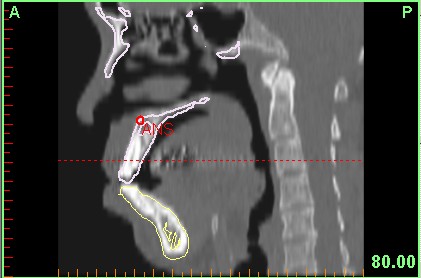

Bilgisayarlı Tomografi, MR, 3 Boyutlu Ultrasonografi gibi farklı görüntüleme tekniklerinin birleştirilmesi ile kişiye özel sert ve yumuşak doku uygulamaları ile sanal ameliyatlar, Kranio Maksillo Fasiel-CMF modulü ile pre-operatif verilerle hastanın post operatif yumuşak doku görüntülemesi, hastanın birebir ölçekli verileri ile 3 boyutlu (3B) katı modelleme ve bu modellerle tüm osteotomi ve distraksiyonun ameliyat öncesi model üzerinde tatbikatı, kişiye özel protez uygulamaları için pek çok ana bilim dalındaki hekim üç boyutlu görüntüleme yazılımı Mimics'i kullanmaktadır.

4C firmasının temsilciliğini yaptığı Mimics yazılım programı ve Z Corp. 3 boyutlu yazıcıları ile hastanın bire bir ölçekli katı modeli üzerinde tüm osteotomiler, vida, plak, distraktör uygulaması, yörüngelerininin doğrulanması, kişiye özel protez tasarımı mümkündür...